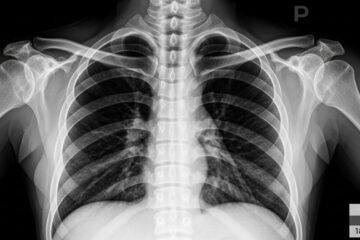

Radiographie Prix Maroc 2026: Tarifs et Guide Complet

Vous cherchez à connaître le prix d’une radiographie au Maroc ? Le coût d’un examen radiologique varie entre 80 DH et 500 DH selon le type d’imagerie médicale, le secteur (public ou privé) et votre ville. En moyenne, une radiographie thoracique coûte entre 100-250 DH, une radio dentaire entre 80-200 DH, et une radiographie osseuse […]